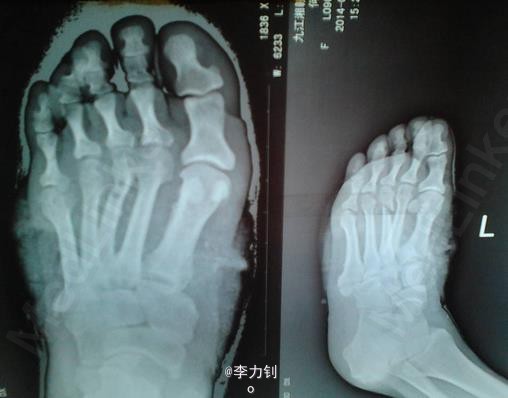

患者,男,48岁,左脚背面机器伤1小时来诊。平素体质一般,无药物、食物过敏史,无高血压、心脏病等系统性疾病。